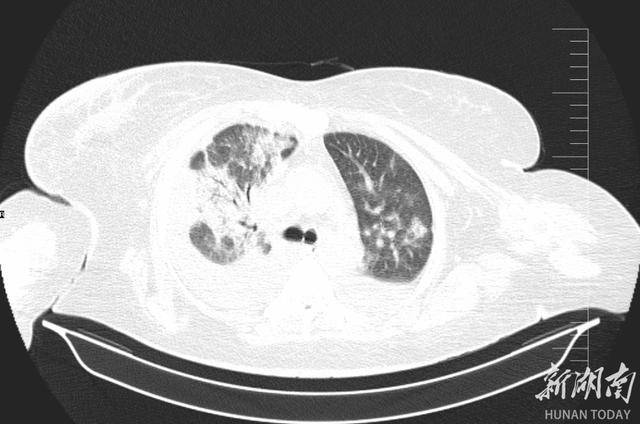

2025 年 12 月 24 日,李阿姨被紧急送入郴州市宜章县人民医院 ICU,她高烧不退、呼吸困难,CT片子上双肺几乎全白了 —— 这是重症肺炎最凶险的信号之一。更麻烦的是,她本身还有肝硬化腹水、十二指肠溃疡大出血等一堆老毛病,所有问题撞在一起,性命危在旦夕。面对如此凶险的病情,救治刻不容缓,ICU 团队火速完成检查并召集多学科会诊,病因被精准锁定:鹦鹉热衣原体感染。

肺部CT可见,重症肺炎较之前大部分被吸收